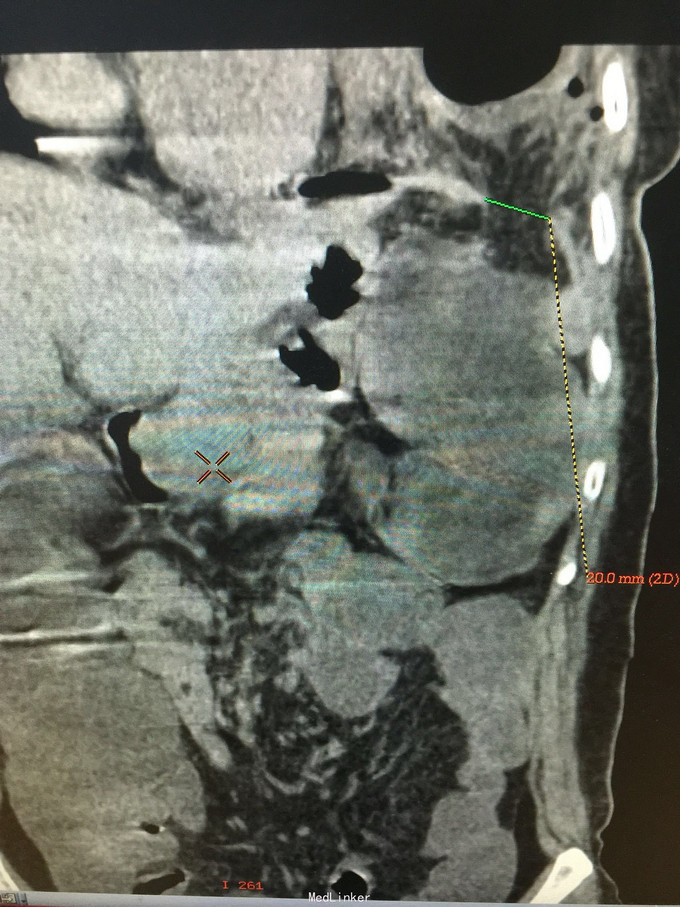

女,41岁, 主诉:腹部胀痛伴不排便、不排气1周, 现病史:一周前无诱因开始腹部胀痛,逐渐加重,以左上腹明显,不排便,不排气,恶心,呕吐数次胃内容物,在当地医院抗炎治疗不见好转,今排腹部平片诊断为“肠梗阻”,来诊。

一般状态可,腹部平坦,未见肠型及蠕动波,脐周压痛,左上腹明显,无腹肌紧张,未及包块,移动性浊音阳性,肠音2次/分。 辅助检查:全腹CT:腹部肠管明显扩张,积液,左侧膈肌局部缺损,腹腔内肠管及系膜组织疝入胸腔。

诊断:膈肌疝,疝内容嵌顿,肠梗阻 处理:手术治疗。

讨论:年轻患者膈肌疝不常见,尤其疝入肠管引起肠梗阻病例更少见;追问病史,该患3年前被刀刺伤左侧季肋部,在外院住院观察,因未见脏器损伤1周后出院,现在考虑为膈肌损伤。